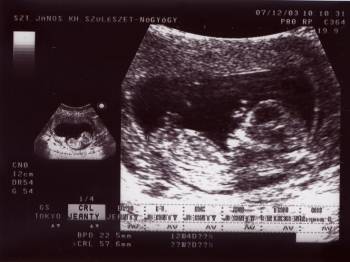

Elan, milyen jó az uh kép! Teljesen kivehető a babó. Az én 12.heti képem olyan béna volt. Csatolom egy kis nosztalgiából...

Gratulálok Kismaszathoz, nagyon jó az UH kép. Én holnap megyek szintén 12 hetes UH-ra, már nagyon izgulok, hogy rendben legyen minden.